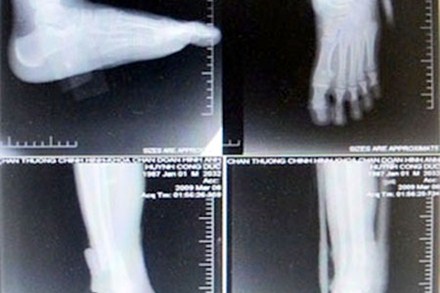

Một bệnh nhân chụp cổ bàn chân ở 4 tư thế đã bị cắt ghép phim.

Việc phát hiện “ăn phim” trên bệnh nhân rất tình cờ, khi một BS làm việc tại BV về thăm người bạn ở Bến Tre. Mẹ của người bạn bị đau vùng vai và cổ đã được người nhà đưa lên BV Chấn thương-chỉnh hình điều trị. Bác sĩ (BS) chỉ định chụp cột sống cổ ở bốn tư thế (thẳng, nghiêng, chếch 3/4 bên trái và bên phải). Bệnh nhân phải nộp 240.000 đồng để mua hai phim chụp X-quang. Tuy nhiên, sau khi xem hồ sơ, vị BS phát hiện phiếu thu tiền chụp phim X-quang cho người bệnh là loại lớn, trong khi hai tấm phim chụp thực tế thì nhỏ, nhìn không rõ. Thay vì phải chụp trên hai phim thì kỹ thuật viên đã ghép cả bốn tư thế chụp trên một phim rồi cắt làm hai, khiến tấm phim bị teo tóp phân nửa (kích thước chỉ còn 35cm x 21,5cm). Từ sự việc trên, nhiều BS của BV tìm hiểu và phát hiện hàng trăm vụ “ăn phim” đã diễn ra tại BV này kéo dài trong nhiều năm.

Theo tố cáo của các BS, khoa CĐHA, BV Chấn thương-chỉnh hình: “Các BS Hồ Văn Thạnh - Trưởng khoa CĐHA, ông Phạm Thanh Hải - Phó khoa và kỹ thuật viên trưởng Bùi Bảo Vinh có hành vi tham ô tài sản. Cụ thể, từ năm 2007 đến nay, nhóm ba người của khoa CĐHA đã chỉ đạo các nhân viên dưới quyền ghép phim, cắt phim, đổi phim, gian lận phim trong việc nhập và xuất phim cho bệnh nhân. Mỗi tháng, khoa này ăn gian của người bệnh gần 250 triệu đồng.  Việc gian lận được thực hiện bằng hai cách: Đánh tráo phim X-quang (thu tiền của bệnh nhân với giá phim loại A, nhưng lại chụp bằng phim loại B rẻ hơn) và lắp ghép phim (người bệnh đóng tiền chụp cho 2 phim, nhưng khoa chụp ghép nhiều bộ phận cơ thể cần chụp trên 1 phim, rồi cắt nhỏ phim ra đưa cho bệnh nhân)”.

Chẳng hạn, bệnh nhân được chỉ định chụp cột sống cổ bốn tư thế: Thẳng, nghiêng, chếch 3/4 hai

bên và BV sẽ thu tiền bệnh nhân là chụp 2 phim. Tuy nhiên, khi chụp, kỹ thuật viên thực hiện việc ghép chụp 2 hoặc 4 phần cơ thể trên một phim. Bệnh nhân hoàn toàn không biết kích thước chuẩn của phim là bao nhiêu, chỉ thấy kết quả chụp X-quang cho ra hình ảnh chụp của bốn tư thế trên cùng một phim của bệnh nhân và giao cho họ nhận 2 tờ phim đã cắt. Bệnh nhân nghĩ là đúng theo phiếu thu tiền 2 phim của BV.